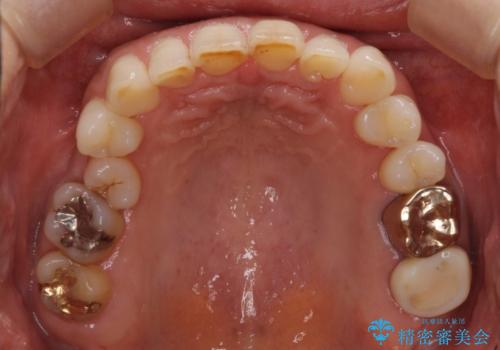

デコボコの歯とむし歯 インビザライン矯正治療とむし歯治療

- 奥歯が咬めないくらいに痛いとのことで来院された患者様です。

痛みの強い歯は、歯髄組織が強い炎症を起こしており、神経を取り除く必要であったため、速やかに根管治療を行いました。

その後、オールセラミッククラウンにて補綴治療を行う予定でしたが、処置した歯以外にも治療が必要と思われる歯があったり、デコボコした歯列も気になるとのことで、患者様希望によりインビザラインにてマウスピース矯正を行うこととしました。

まずは矯正治療前に必要なむし歯処置を行い、その後矯正治療を行ってから、最後にオールセラミッククラウンなどで補綴治療を行うこととしました。

咬合力が非常に強く、全体的に歯が擦り減っている状態であったので、理想的な咬み合わせを達成することは難しく、また咬合力が強い方のマウスピース矯正は、思い通りに動かないことがあるため、ワイヤー矯正の方が望ましいように思えました。